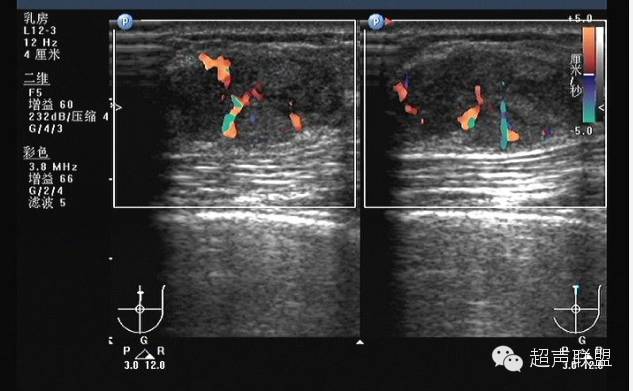

5.多普勒灵敏度和功率多普勒技术的改善,使观察乳腺内部的血管分布更为直接。在20世纪80年代初多普勒超声技术刚用于血管检测时,主要采用连续波多普勒,因为它有较高的灵敏度。乳腺肿块周围的血管内含有较高的血流速度被认为是恶性肿瘤的象征。现在,只需用彩色多普勒观察分布于肿块内外的血管数量即可作出同样的诊断。尽管对于多普勒信息的解释仍有异议,但多数研究者及ATL/FDA临床实验的结果确认了乳腺肿块中增加的血管分布预示了恶性肿瘤。